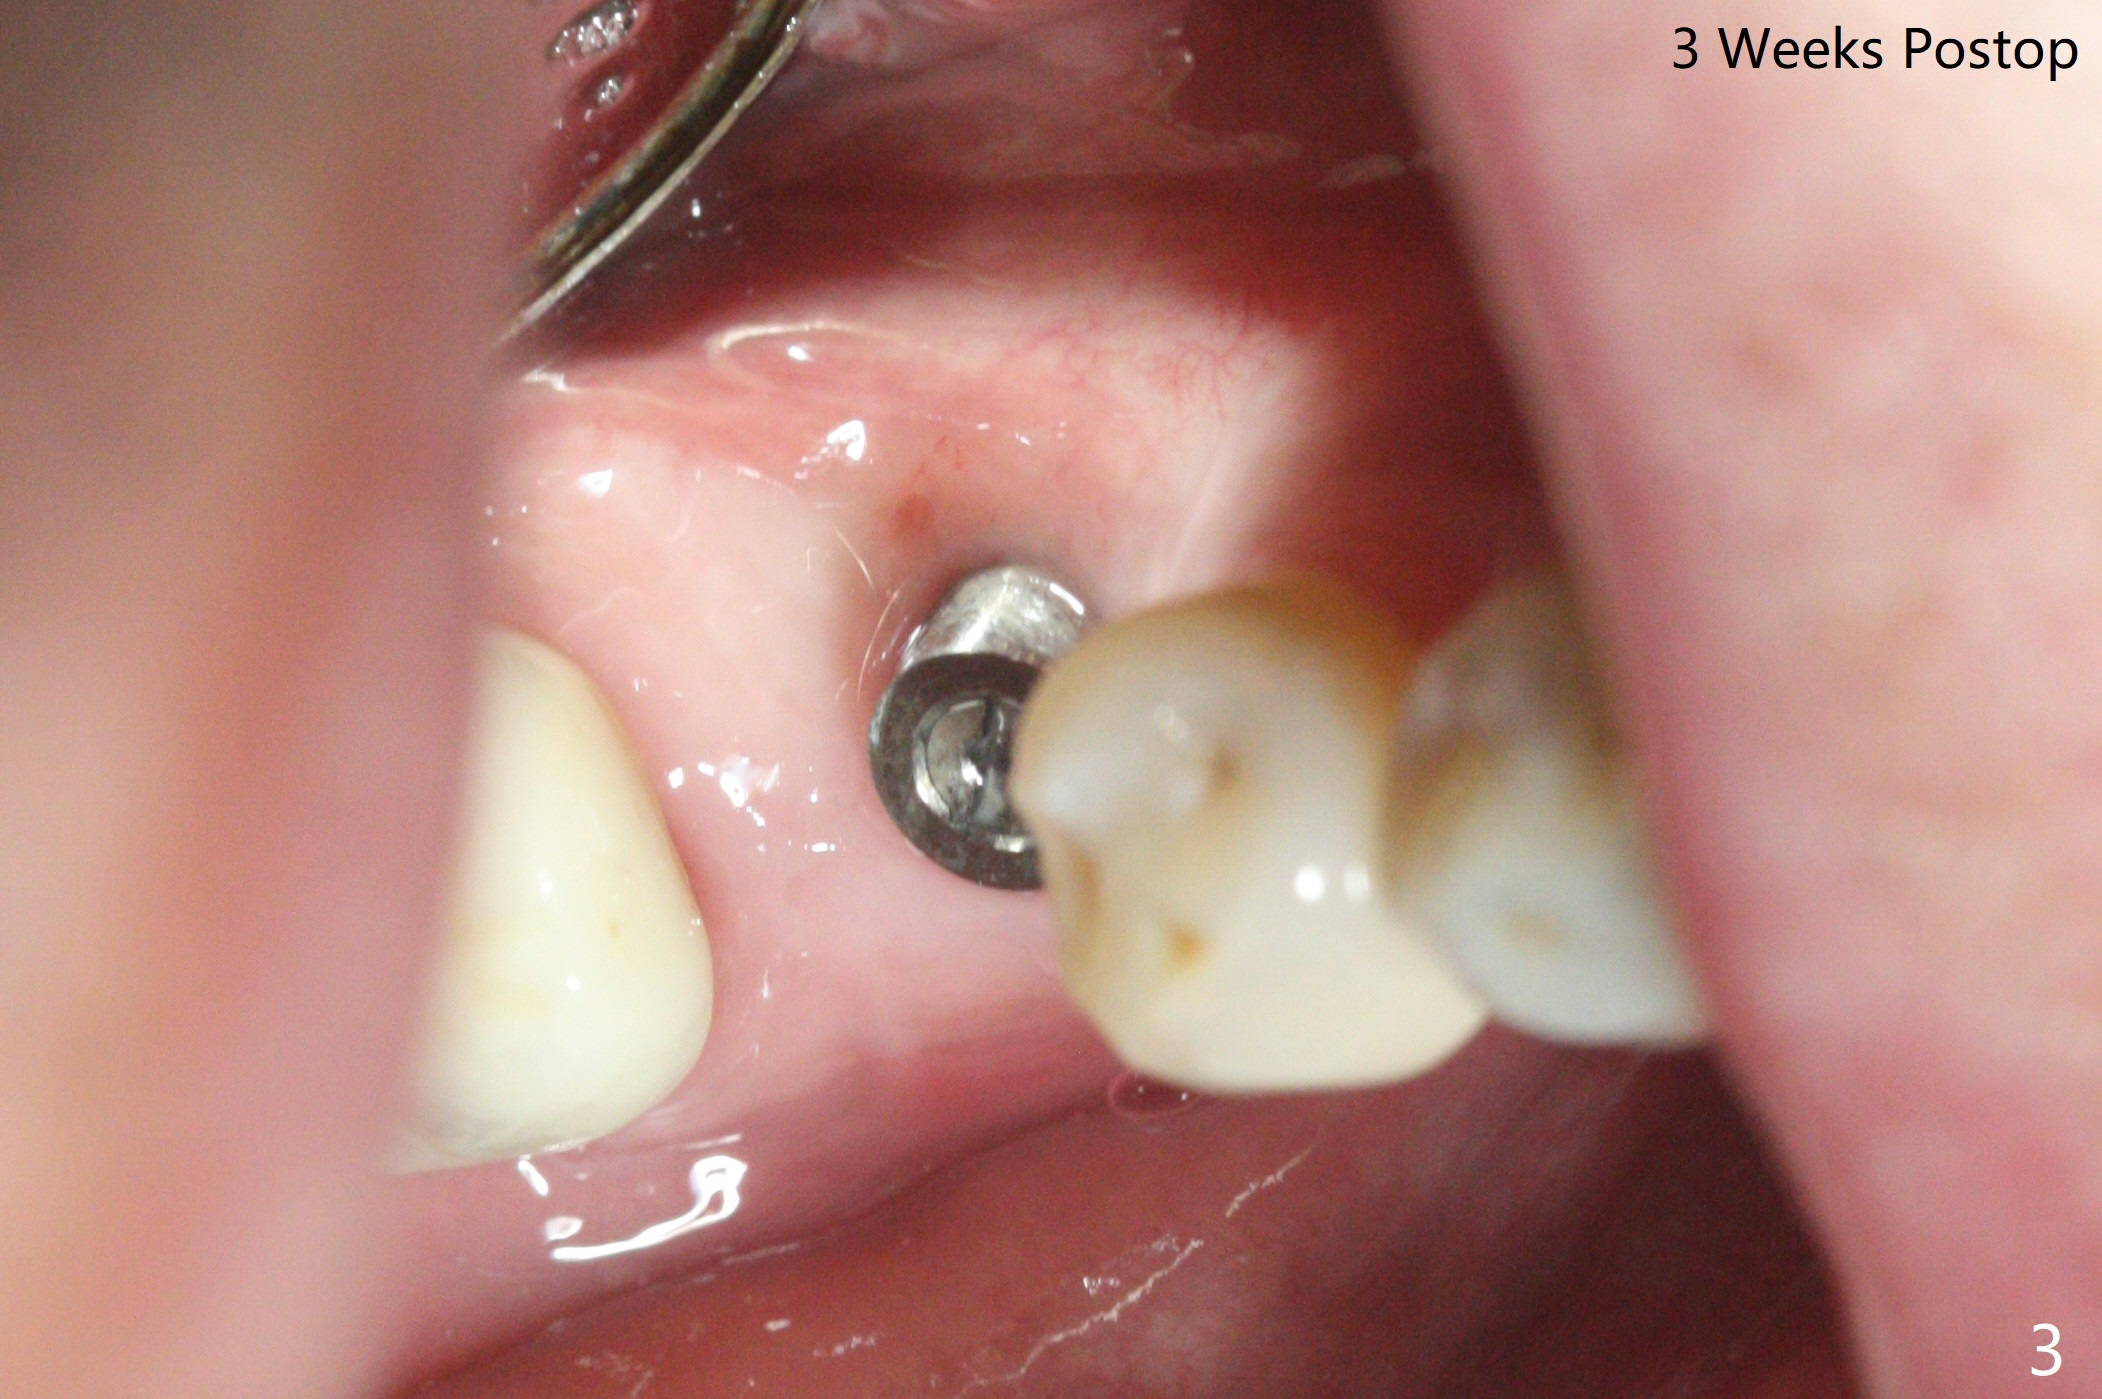

右下第一磨牙植体取出,植骨5.5月后,植牙区颊侧角化龈多,使用环形刀开始导板钻洞,最后徒手种植(图一),美中不足植体植体舌侧粗糙面暴露,一直到术后三周(图二,三),而且接近非角化龈(N;(K: 角化龈)),这可能与舌侧牙槽嵴斜坡比较陡有关,如果术前注意到这一点,术中又使用环形刀定位,切开导板种植,问题便可以避免。准备术后3个月拍摄CT,证实舌侧螺纹是否裸露。如果不明显,使用愈合袖(healing cuff),方便取模。